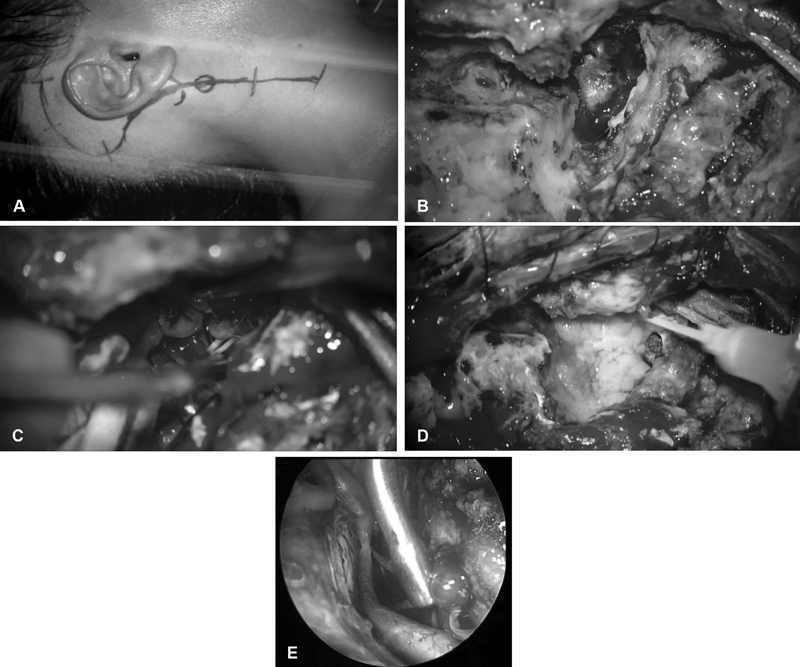

图2,外科手术的步骤。(A)沿胸锁乳突肌前缘切口,穿过乳突上方。(B)切除钻取枕髁和乳突后的肿瘤包膜视图。(C)从对侧颈静脉孔的神经进行硬膜内肿瘤剥离。(D)使用游离脂肪移植物闭合硬膜缺损。(E)内镜硬膜内探查显示对侧颈静脉孔有肿瘤残留,需要继续进行肿瘤切除。